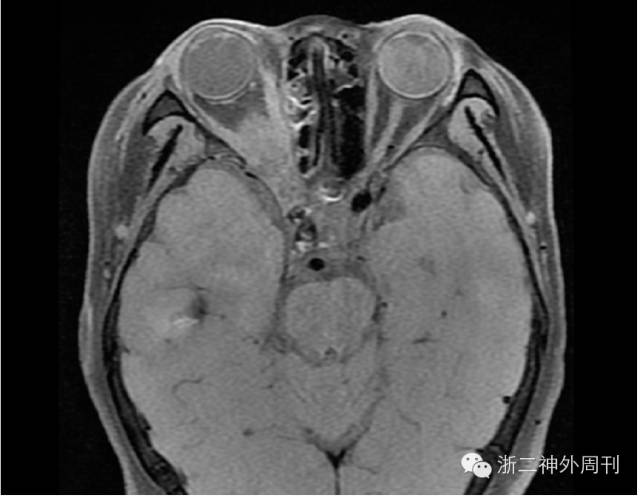

术后予抗凝、扩容等处理,患者病情平稳,次日头颅MRI+DWI复查,未见明显梗塞灶,但异物残留明显(图8)。

图8. 闭塞后DWI检查未见缺血梗塞发生,异物残留明显。